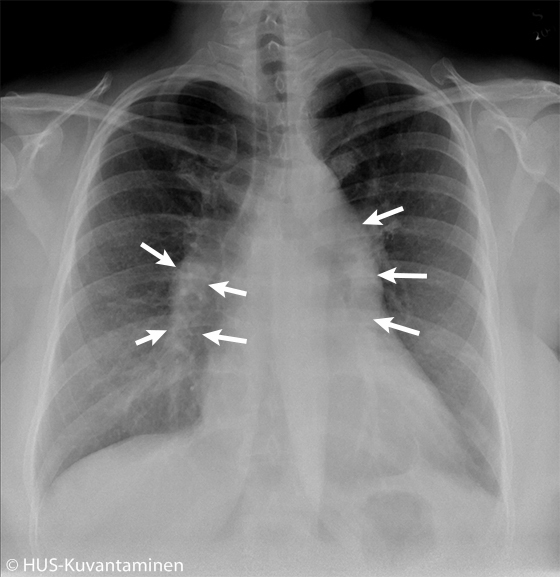

Kohonnut keuhkoverenpaine (kuva löydösmerkinnöin).

Keuhkokuvassa näkyvät kohonneeseen keuhkoverenpaineeseen sopivat löydökset. Lisäksi keuhkovaltimot ovat prominentit (nuolten väliin jäävä alue).

Kuva: HUS-Kuvantaminen